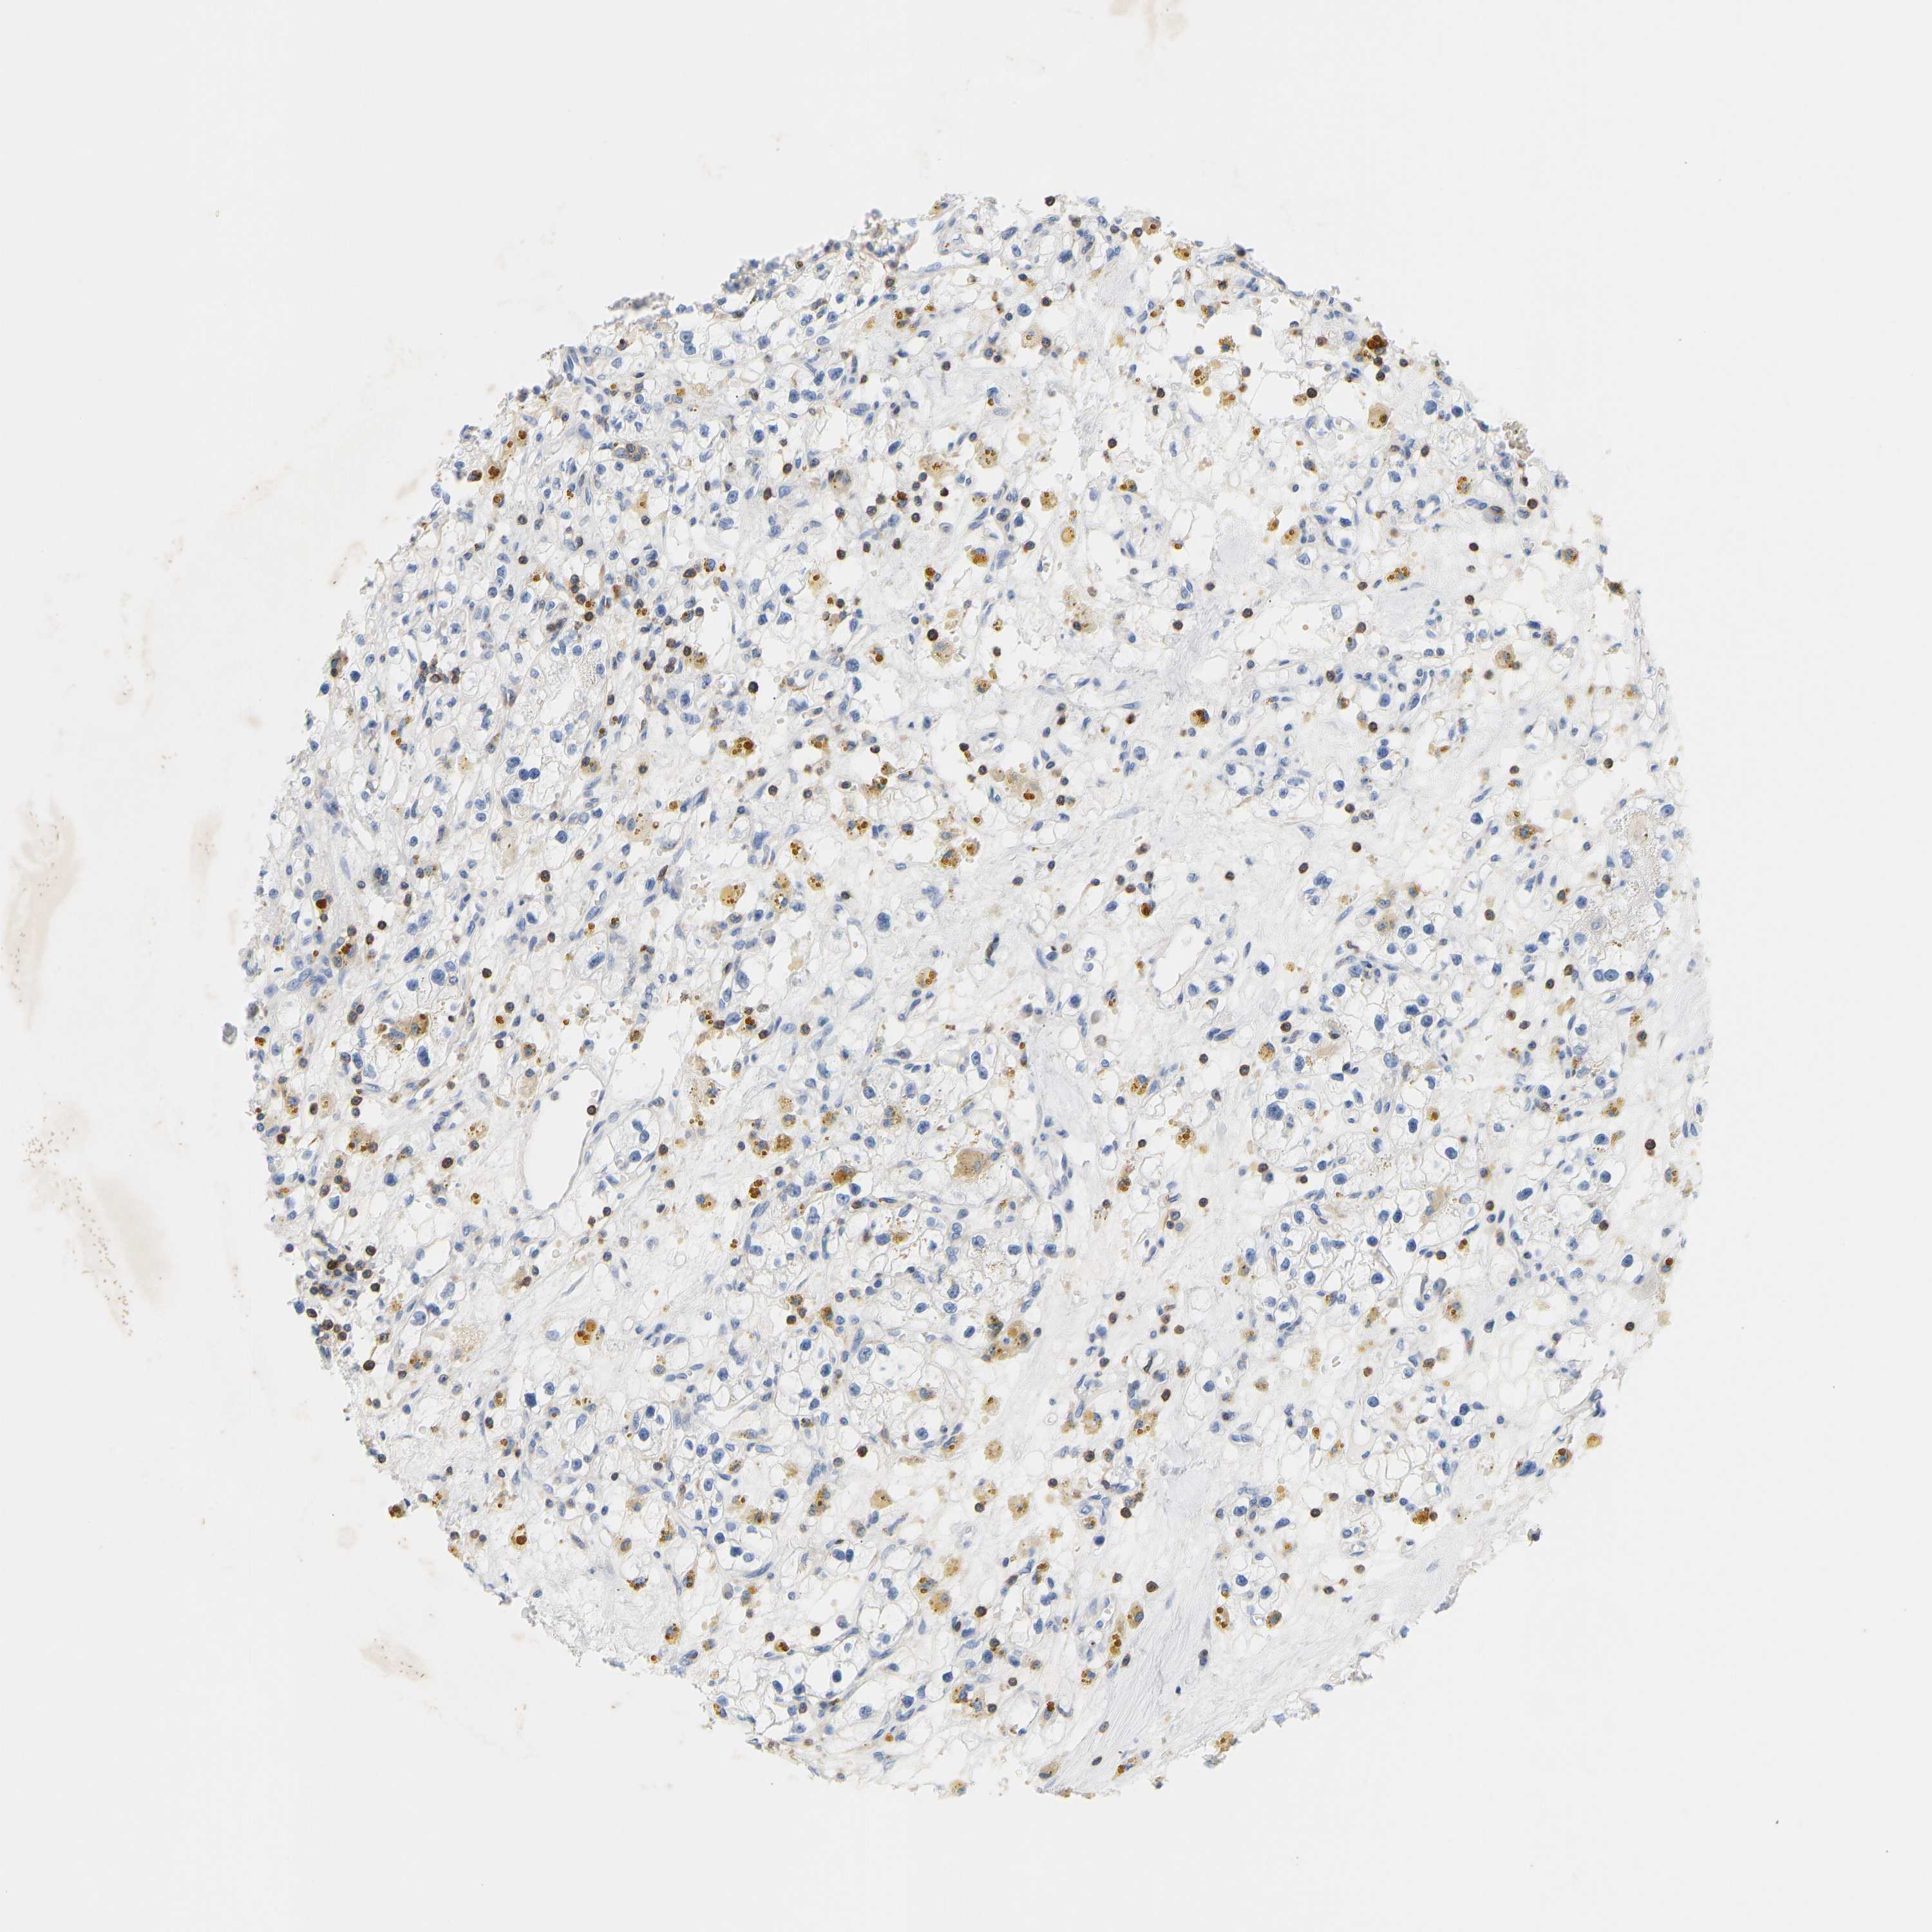

KIDNEY RENAL PAPILLARY CELL CARCINOMA (TCGA) - Interactive survival scatter ploti

The Survival Scatter plot shows the clinical status (i.e. dead or alive) for all individuals in the patient cohort, based on the same data that underlies the corresponding Kaplan-Meier plots. Patients that are alive at last time for follow-up are shown in blue and patients who have died during the study are shown in red.

The x-axis shows the expression levels (FPKM) of the investigated gene in the tumor tissue at the time of diagnosis. The y-axis shows the follow-up time after diagnosis (years). Both axes are complimented with kernel density curves demonstrating the data density over the axes. The top density plot shows the expression levels (FPKM) distribution among dead (red) and alive patients (blue). The right density plot shows the data density of the survived years of dead patients with high and low expression levels respectively, stratified using the cutoff indicated by the vertical dashed line through the Survival Scatter plot. This cutoff is automatically defined based on the FPKM cutoff that minimizes the p-score. The cutoff can be changed by dragging the vertical line or by entering a cutoff value in the square labeled "Current cut-off".

Under the Survival Scatter plot the p-score landscape (black curve; left axis) is shown together with dead median separation (red curve; right axis). Dead median separation is the difference in median mRNA expression between patients who have died with high and low expression, respectively. It is calculated as follows: median FPKM expression of dead patients with high expression - median FPKM expression of dead patients with low expression. This is intended to aid the user in visually exploring custom cutoffs and the associated p-scores and dead median separation.

Individual patient data is displayed and can be filtered by clicking on one or more of the category buttons on the top of the page. Categories describing expression level and patient information include: high, low, alive, dead, female, male and tumor stages. The scale of the x-axis can be toggled between linear and log-scale by clicking on the "x log" button. Mouse-over function shows TCGA ID, patient information and mRNA expression (FPKM) for each patient.

& Survival analysisi

Kaplan-Meier plots summarize results from analysis of correlation between mRNA expression level and patient survival. Patients were divided based on level of expression into one of the two groups "low" (under cut off) or "high" (over cut off). X-axis shows time for survival (years) and y-axis shows the probability of survival, where 1.0 corresponds to 100 percent.

EVL is potential prognostic, high expression is favorable in Kidney Renal Papillary Cell Carcinoma (TCGA)